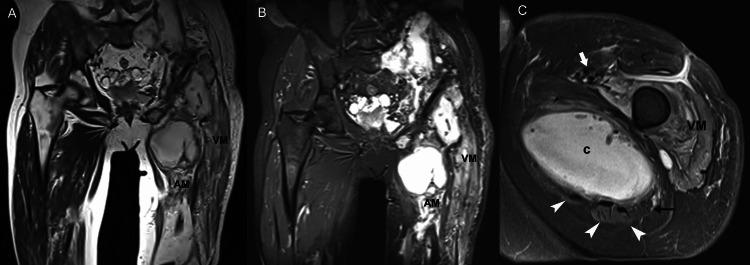

Skeletal muscle is a major anatomic structural component of the human body. Myopathy, defined as skeletal muscle disease, may offend any of the body's 650 muscles and encompasses an extended array of acute and chronic abnormalities. Muscle disease can be categorized according to etiology as congenital, traumatic, infectious, or neoplastic. The concept of the diversity of multiple muscular disease processes signifies an important role for imaging in the detection and characterization of myopathy. However, despite the exquisite physiological properties of skeletal muscle, muscle imaging has not received attention equal to that of bones and joints. Accordingly, this article provides an indication of the most suitable imaging modalities for myopathy and reviews a multitude of primary and systemic muscle derangements, with an emphasis on magnetic resonance (MR) imaging findings. Because these patterns of MR imaging abnormality bespeak the widespread nature of myopathy, we illustrate typical examples of muscle disease processes to simplify diagnosis.

骨骼肌是人体主要的解剖结构组成部分。肌病,定义为骨骼肌疾病,可累及人体650块肌肉中的任何一块,涵盖一系列急性和慢性异常情况。肌肉疾病可根据病因分为先天性、创伤性、感染性或肿瘤性。多种肌肉疾病过程的多样性概念表明成像在肌病的检测和特征描述中具有重要作用。然而,尽管骨骼肌具有精细的生理特性,但肌肉成像并未得到与骨骼和关节成像同等的关注。因此,本文指出了最适合用于肌病的成像方式,并综述了多种原发性和全身性肌肉紊乱,重点关注磁共振(MR)成像表现。由于这些MR成像异常模式表明肌病具有广泛的性质,我们展示了肌肉疾病过程的典型例子以简化诊断。